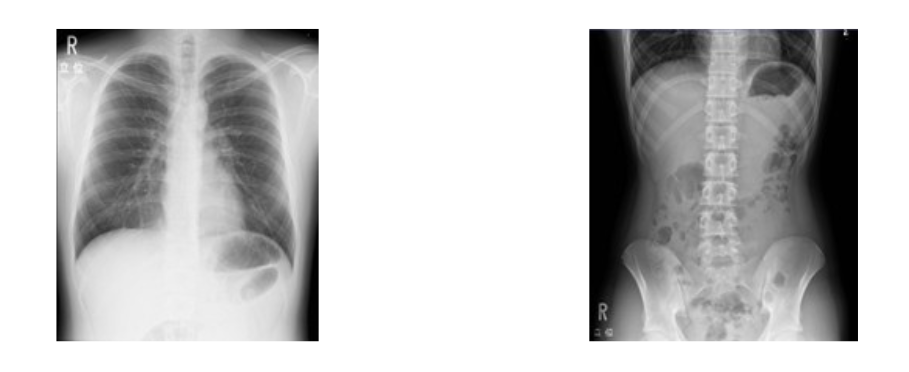

【胸部】 【腹部】

【手】 【膝関節】

胸部撮影では、肺に異常な影があるかどうか、心臓の形に異常があるかどうかを調べます。

腹部撮影では、炎症や石灰化、腸管内のガスや食物残渣の有無、尿路結石や腹水などの疾患を調べます。

骨の撮影では、骨、関節、靭帯の状態や機能、筋肉、脂肪組織の状態を調べます。骨折、脱臼、変形などがわかります。